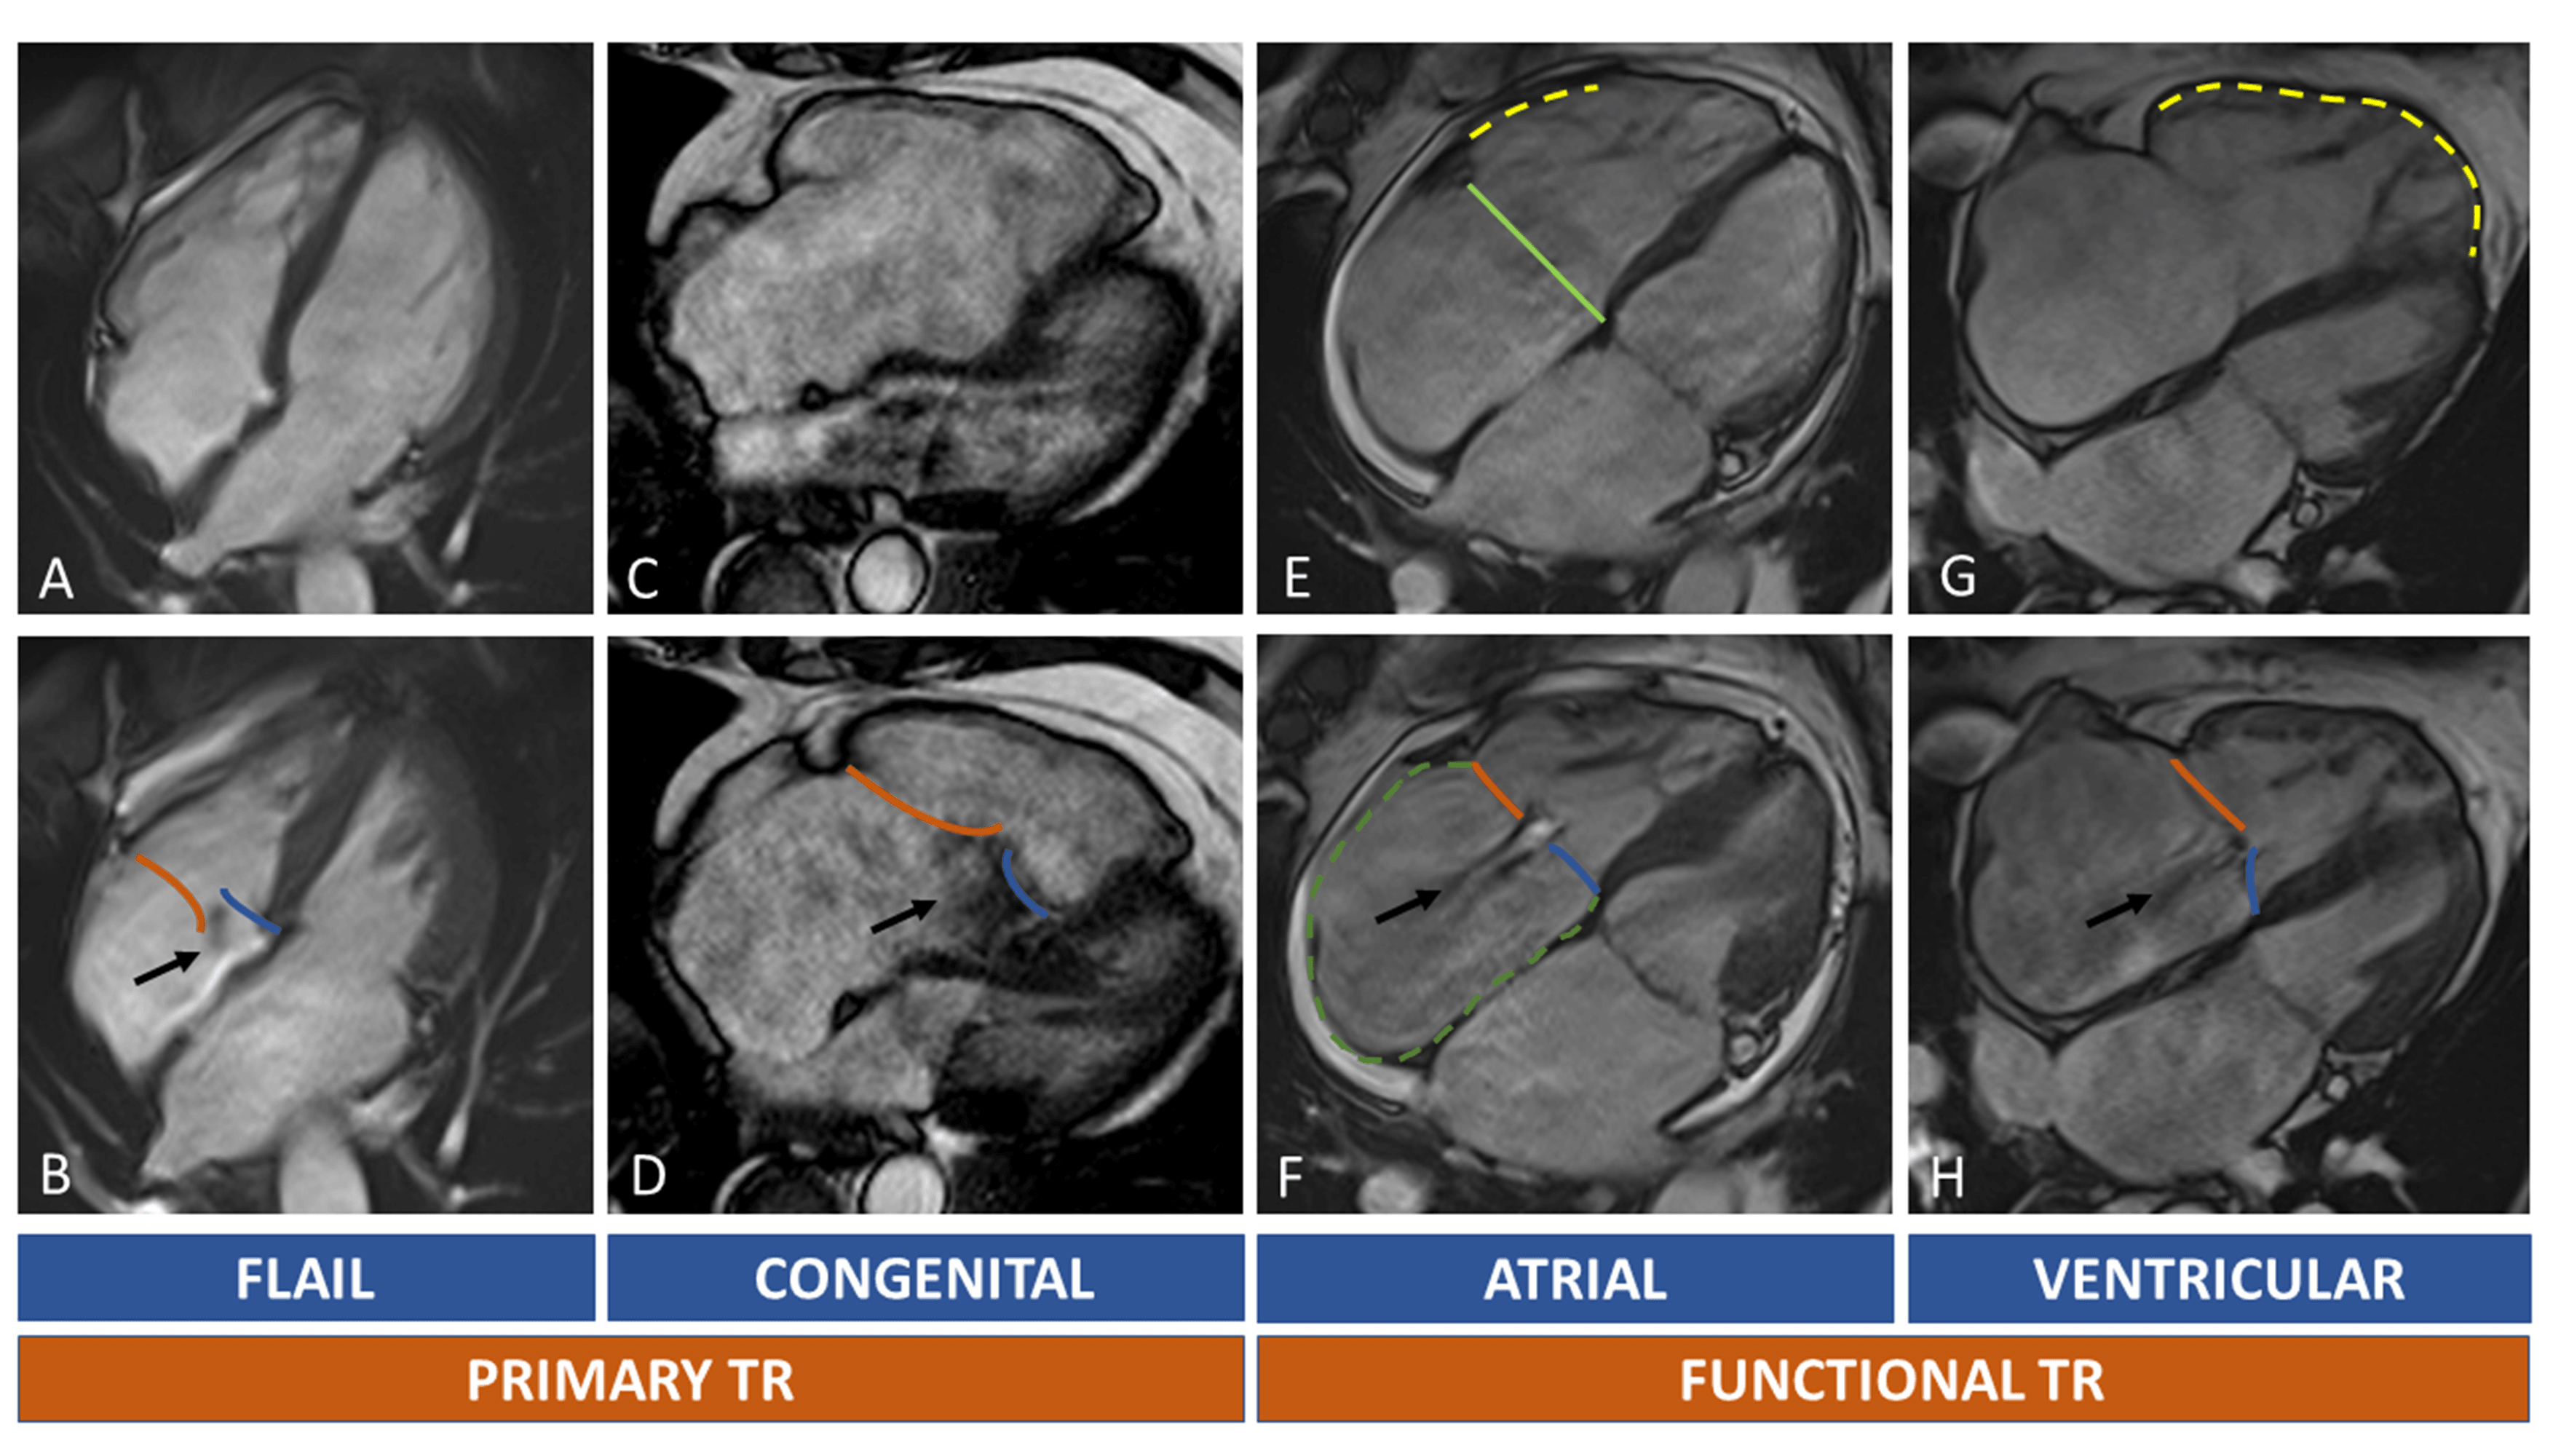

CT scan is pivotal for the pre-procedural planning of TTVI. Transcatheter tricuspid devices can be categorized as: coaptation devices, annuloplasty devices, heterotopic valves, orthotopic prostheses (Table 7A,7B).

| Coaptation devices: Blue star: anatomical regurgitant orifice area (AROA), can

be traced from SAX of TV; Blue line: coaptation gap calculated from 4 chamber

view; Blue arrowheads indicate inferior and superior vena cava. Forma Device: Continuous circular blue line represents 2D planar contouring of TA; dotted blue line indicates TA; red line is the distance between TA and anchoring point of Forma device to apical septum; yellow line represents the distance between the anterior papillary muscle (APM) and the interventricular septum; purple little line indicates the distance between APM and the TA. Annuloplasty devices: Right coronary artery course and distance from TA must be described before device annuloplasty. RCA course can be in the AV groove (*), superior to TA (up arrowhead) or inferior to TA (down arrowhead). The RCA (in red in the 3D model) is indicated by red arrows in 4 chamber and RV inflow/outflow view. Critical distance points between RCA and TA are highlighted by yellow stars and they refer to proximal and distal RCA, sites of possible injury during the procedure. Abbreviations: APM, anterior papillary muscle; CT, computed tomography; RCA, right coronary artery; RV, right ventricle; TA, tricuspid annulus. |

Coaptation devices are based on edge-to-edge and edge-spacer-edge valve repair [33, 117]. Patient’s selection for the most commonly available coaptation devices, Triclip (Abbott Vascular, Santa Clara, CA, USA) and Pascal (Edwards Lifesciences, Irvine, CA, USA), rely exclusively on echocardiographic evaluation and CCT is not necessary. However, lead position, leaflets calcifications and the presence of unfavourable angles between IVC and TA can be easily assessed by CCT images during pre-procedural planning. Moreover, in case of inconclusive echocardiographic data, coaptation gap and leaflets length can be measured and TTVI strategy can be changed in case of large coaptation gap or extreme tethering unsuitable for TEER. The Forma spacer device (Edwards Lifesciences, Irvine, CA, USA) is another kind of edge-to spacer device based on a foam-filled polymer balloon that fills the leaflets coaptation gap. The anchoring system is placed in the right ventricular apex, the spacer is placed at the annular level into the coaptation gap, and then the system is then locked in subclavian region. Device sizing is based on coaptation gap and TA dimensions, while the distance between TA and RV apex, as well as between TA and papillary muscles are assessed for device suitability and to avoid anchoring problems (Table 7A). The Forma system requires a large 24F sheath, hence CT scan is useful also to assess adequate dimensions and patency of left subclavian and axillary veins [118].

The goal of annuloplasty devices is to reduce TA area in FTR. Trialing, TriCinch, Cardioband and Traipta systems are some of the annuloplasty devices currently accessible [119, 120, 121, 122] (Table 7A). Right coronary artery (RCA) complications occur in 15% of patients treated with Cardioband [123] and are considered a major worry in transcatheter annuloplasty. Cardioband anchors are placed in the periannular tissue, and the risk of coronary injury depends on the course and the distance of the RCA around the TA (Fig. 7). The use of a triphasic contrast medium administration protocol may allow to achieve a good visualization of right heart and coronary arteries at the same time. In a study of 250 patients with TR who underwent CT evaluation, the course of RCA had 3 main configurations: along the TA (65% of patients), superior to TA (10%) and crossing the TV (25%). Distance between RCA and TA was measured in mid-diastole, using either a SAX view of the TA in case of RCA running at the same level or a long axis view in case of superior or inferior course. The authors suggest that a maximal distance between the anterior or posterior part of the TA (at the level of the anterior or posterior leaflet insertion) and the proximal or distal RCA of 2 mm, may be associated with high risk of RCA impingement [111]. In the TriCinch device, a corkscrew delivery system is advanced through femoral access to the target region of TA, where the coil is implanted. The target zone is the antero-posterior commissure of TA (at 9–10 o’clock with a ventricular en-face view of TV); at this level, the distance between TA and RCA must be assessed. Among the first 18 patients implanted, RCA injury occurred in one patient. Instead, the goal of the Trialign system is the bicuspidalization of TV, obtained by positioning two pledgets in the septo-posterior and antero-posterior commissures; the two pledgets are then approximated to reduce annular size and regurgitant orifice area. In the first trial, RCA damage requiring stenting occurred in about 6% of cases, with the proximal RCA near to the antero-posterior commissure being the area at higher risk. Finally, the Transatrial intrapericardial tricuspid annuloplasty (TRAIPTA) consists of an indirect annuloplasty repair thorough a loop delivered along the atrioventricular groove within the pericardial space, which is reached by puncturing of right atrial appendage (RAA). Relationship between RAA and the surrounding structures must be evaluated during pre-operative CT planning.